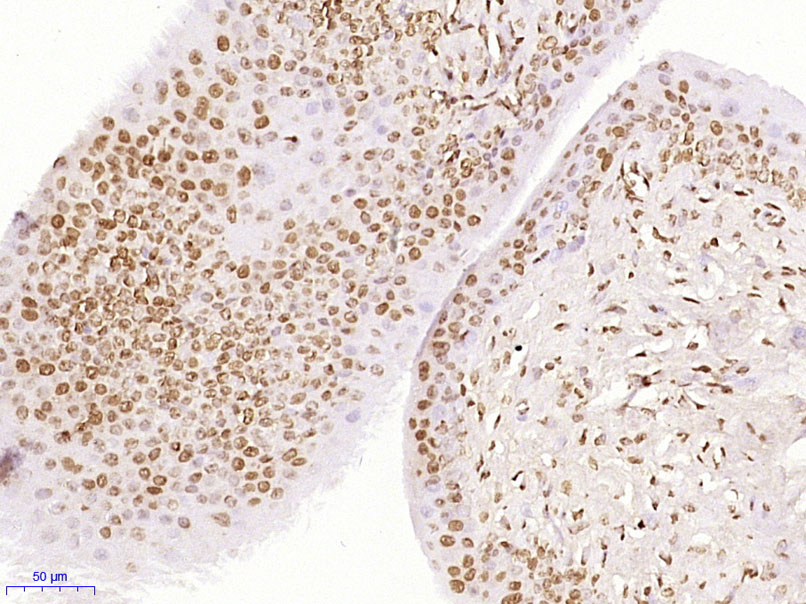

Paraformaldehyde-fixed, paraffin embedded (Rat bladder); Antigen retrieval by boiling in sodium citrate buffer (pH6.0) for 15min; Block endogenous peroxidase by 3% hydrogen peroxide for 20 minutes; Blocking buffer (normal goat serum) at 37°C for 30min; Antibody incubation with (ZFP64) Polyclonal Antibody, Unconjugated (bs-19129R) at 1:400 overnight at 4°C, followed by operating according to SP Kit(Rabbit) (sp-0023) instructionsand DAB staining.

Paraformaldehyde-fixed, paraffin embedded (Mouse brain); Antigen retrieval by boiling in sodium citrate buffer (pH6.0) for 15min; Block endogenous peroxidase by 3% hydrogen peroxide for 20 minutes; Blocking buffer (normal goat serum) at 37°C for 30min; Antibody incubation with (ZFP64) Polyclonal Antibody, Unconjugated (bs-19129R) at 1:400 overnight at 4°C, followed by operating according to SP Kit(Rabbit) (sp-0023) instructionsand DAB staining.